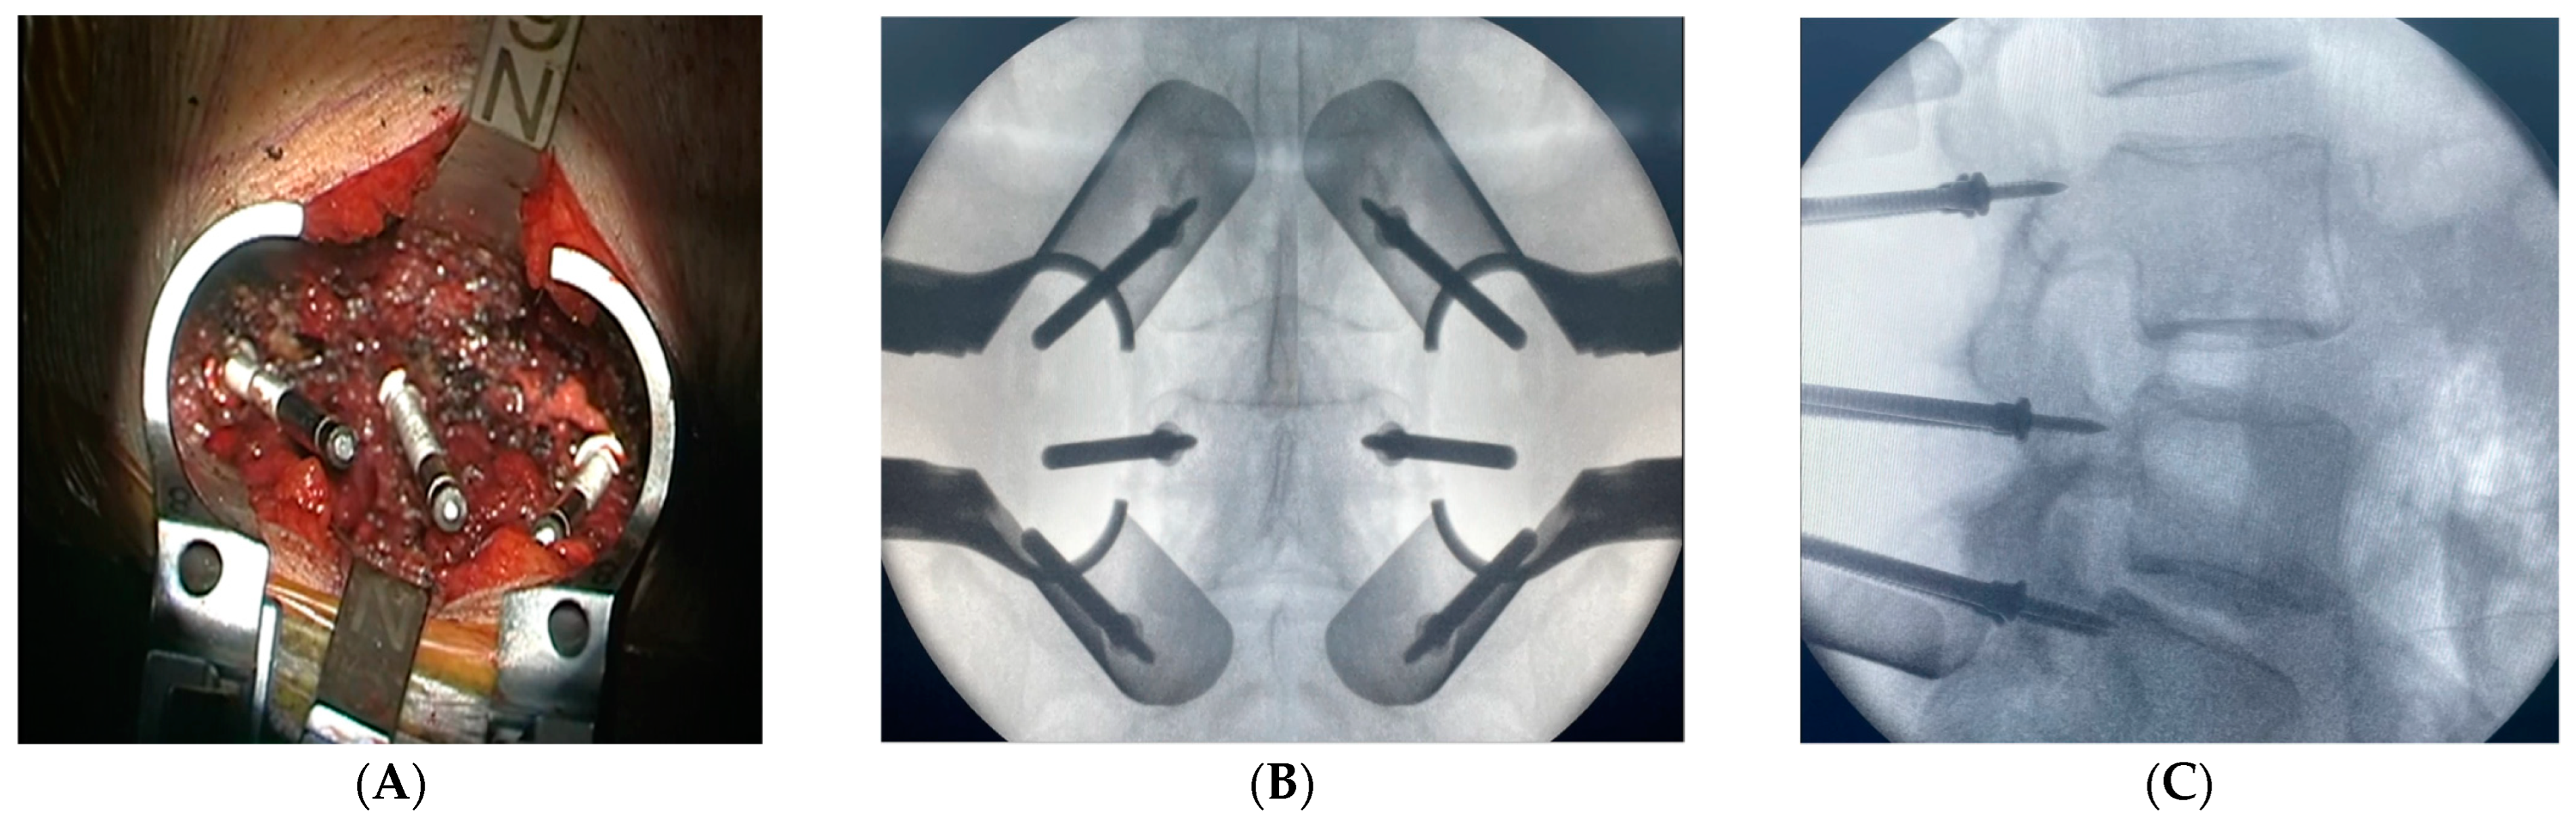

2.3. Surgical Intervention and Marker Screw Utilization